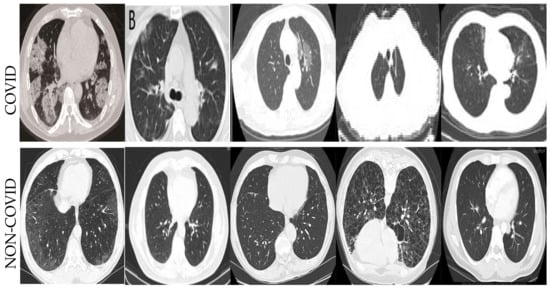

- We employ the deep learning algorithms for COVID-19 datasets to detect infection in the CT and X-ray images;

4.2. Datasets